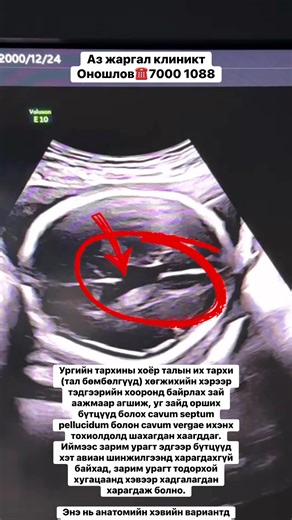

Ultrasound - Cavum Septum Pellucidum

Septum Pellucidum - Cavum Septum Pellucidum

Et Vergae - Cavum Septum Pellucidum

Fetal Ultrasound - Deviated Nasal

Vergae Is Noted - Septal